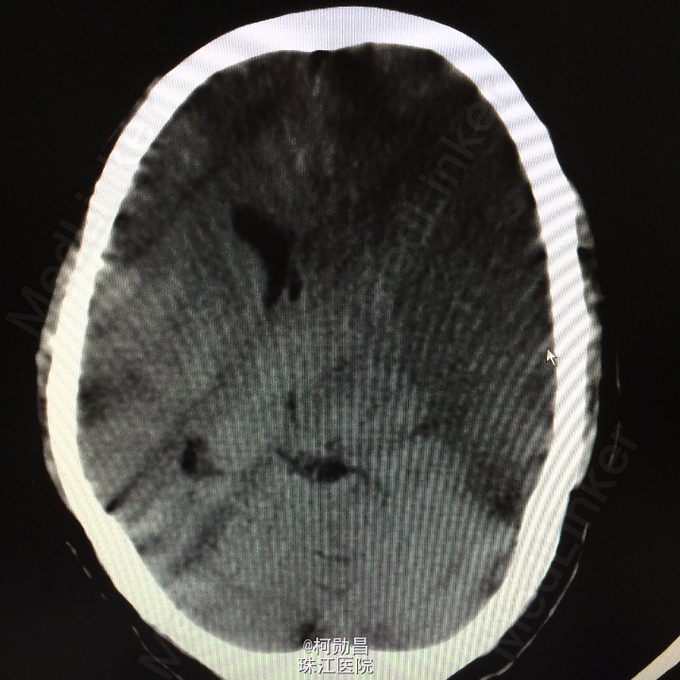

主诉:突发言语不能伴右侧肢体无力1天余 病史:患者于1天前无明显诱因突发言语不能,伴右侧肢体无力,表现为右侧肢体不能自主活动,无头痛头晕,无恶心呕吐,无肢体麻木、四肢抽搐、意识不清等症状。于当地医院就诊,查头颅CT提示:未见异常,予对症支持治疗,症状无好转。半天前患者症状加重,出现神志不清,呈嗜睡状态,现患者为求进一步诊治,遂至我院。门诊拟以“大面积脑梗塞”收入院。

查体:神志呈昏睡状态,言语不能,精神差,双侧瞳孔不等大,左侧3mm,对光反射消失;右侧瞳孔2,mm,对光反射灵敏,右侧肢体肌力0级,左侧肢体肌力5级,右侧肢体肌张力减低,余未见异常。 辅助检查:左侧大脑半球累计岛叶、基底节区(以颞顶叶为主)大片状低密度影,考虑脑梗塞;中线结构明显右移。

诊断:大面积脑梗 处理:予对症支持治疗,运用抗血小板治疗,抗凝治疗